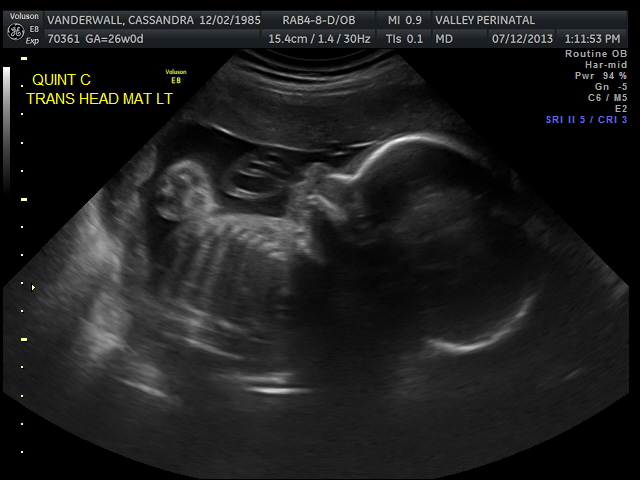

Friday we surpassed yet another milestone! The babies have been cooking for 7 months, which means we are now above the average gestational age for quintuplets. All of the babies were measured on Friday and they are all measuring within a day or two of the recommended size for babies at this point in pregnancy.

All of their organs (kidneys, bladders, hearts, brains, stomachs) look great and are also appropriate sizes. The blood flow to Elle has improved and has stabilized. All heart rates remain within normal limits, and are often on the higher side, which is probably because they just can’t sit still. We are truly excited to meet our little wiggle worms!